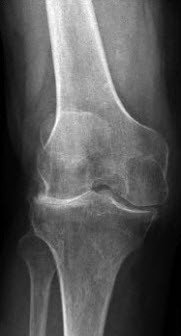

Osteoarthritis of the knee

Osteoarthritis, a degenerative and mostly age-related wearing of the cartilage surfaces, causes inflammation and therefore pain in the knee. Gradually, the bone structure is damaged further and mobility is significantly restricted. Osteoarthritis cannot be healed and it usually progresses until the knee joint is completely destroyed. Wear of the knee joint is the most common reason for knee joint replacement.

Osteoarthritis can also develop as the result of inflammatory rheumatism or years after knee injuries or after meniscus surgery. The extent of the knee pain, limping and the associated disability are key factors in a patient’s decision to consult the doctor. This suffering, more so than age, is a critical consideration when deciding to implant an artificial knee joint. An important prerequisite is that all conservative and therapeutic (non-surgical) measures currently available have been exhausted or no longer have any effect.